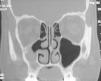

La exploración clínica fue normal. No se observó tumefacción ni palidez de la mucosa nasal. Tampoco se apreciaban asimetrías faciales. La exploración endoscópica nasal revelaba un discreto desplazamiento lateral de la apófisis unciforme. Los resultados de prick-test fueron negativos. La radiografía de tórax no mostraba alteraciones patológicas. En la radiografía de senos paranasales se apreciaba una ocupación completa del seno maxilar derecho, por lo que fue diagnosticada de sinusitis maxilar, y se le pautó tratamiento antibiótico. En la radiografía realizada 2 semanas más tarde se mantenía la imagen de ocupación, por lo que se decidió realizar una TC, en la que se apreciaba una opacificación parcial del seno maxilar derecho, con desplazamiento lateral de la pared infundibular medial, con incipiente descenso de la pared orbitaria inferior y retracción de la mucosa del meato medio, sin niveles hidroaéreos endosinusales (figs. 1 y 2). Dada la ausencia de signos, síntomas y complicaciones, la actitud terapéutica ha sido expectante. Si se produjera una evolución hacia el enoftalmos, se propondría tratamiento quirúrgico dirigido a la liberación del ostium del seno maxilar.

Figura 1.TC de senos paranasales (proyección coronal) en la que se observan los criterios diagnósticos típicos: opacificación y disminución de tamaño del seno maxilar, desviación lateral de la pared infundibular medial y retracción de la mucosa sinusal.

Los criterios diagnósticos radiológicos de ACM incluyen opacificación del seno maxilar, desviación lateral de la pared infundibular medial y retracción de la mucosa sinusal 3-5,9-11. Estos criterios están presentes en el caso que aportamos (figs. 1 y 2).